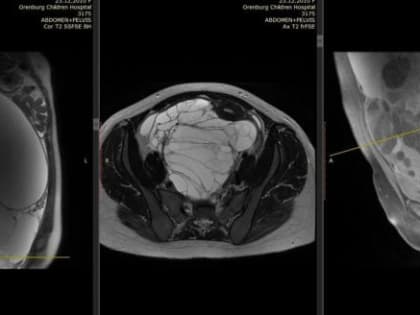

В Оренбурге хирурги успешно удалили опухоль весом 8 кг у 13-летней девочки

Медики провели сложную операцию, вернув здоровье ребенку.

Уникальная операция в Оренбурге: девочке удалили гигантскую опухоль

В Оренбургской детской больнице успешно проведена сложнейшая операция на яичнике.

Оренбургские врачи успешно удалили гигантскую опухоль у подростка

13-летняя девочка избавилась от 8-килограммовой цистаденомы.